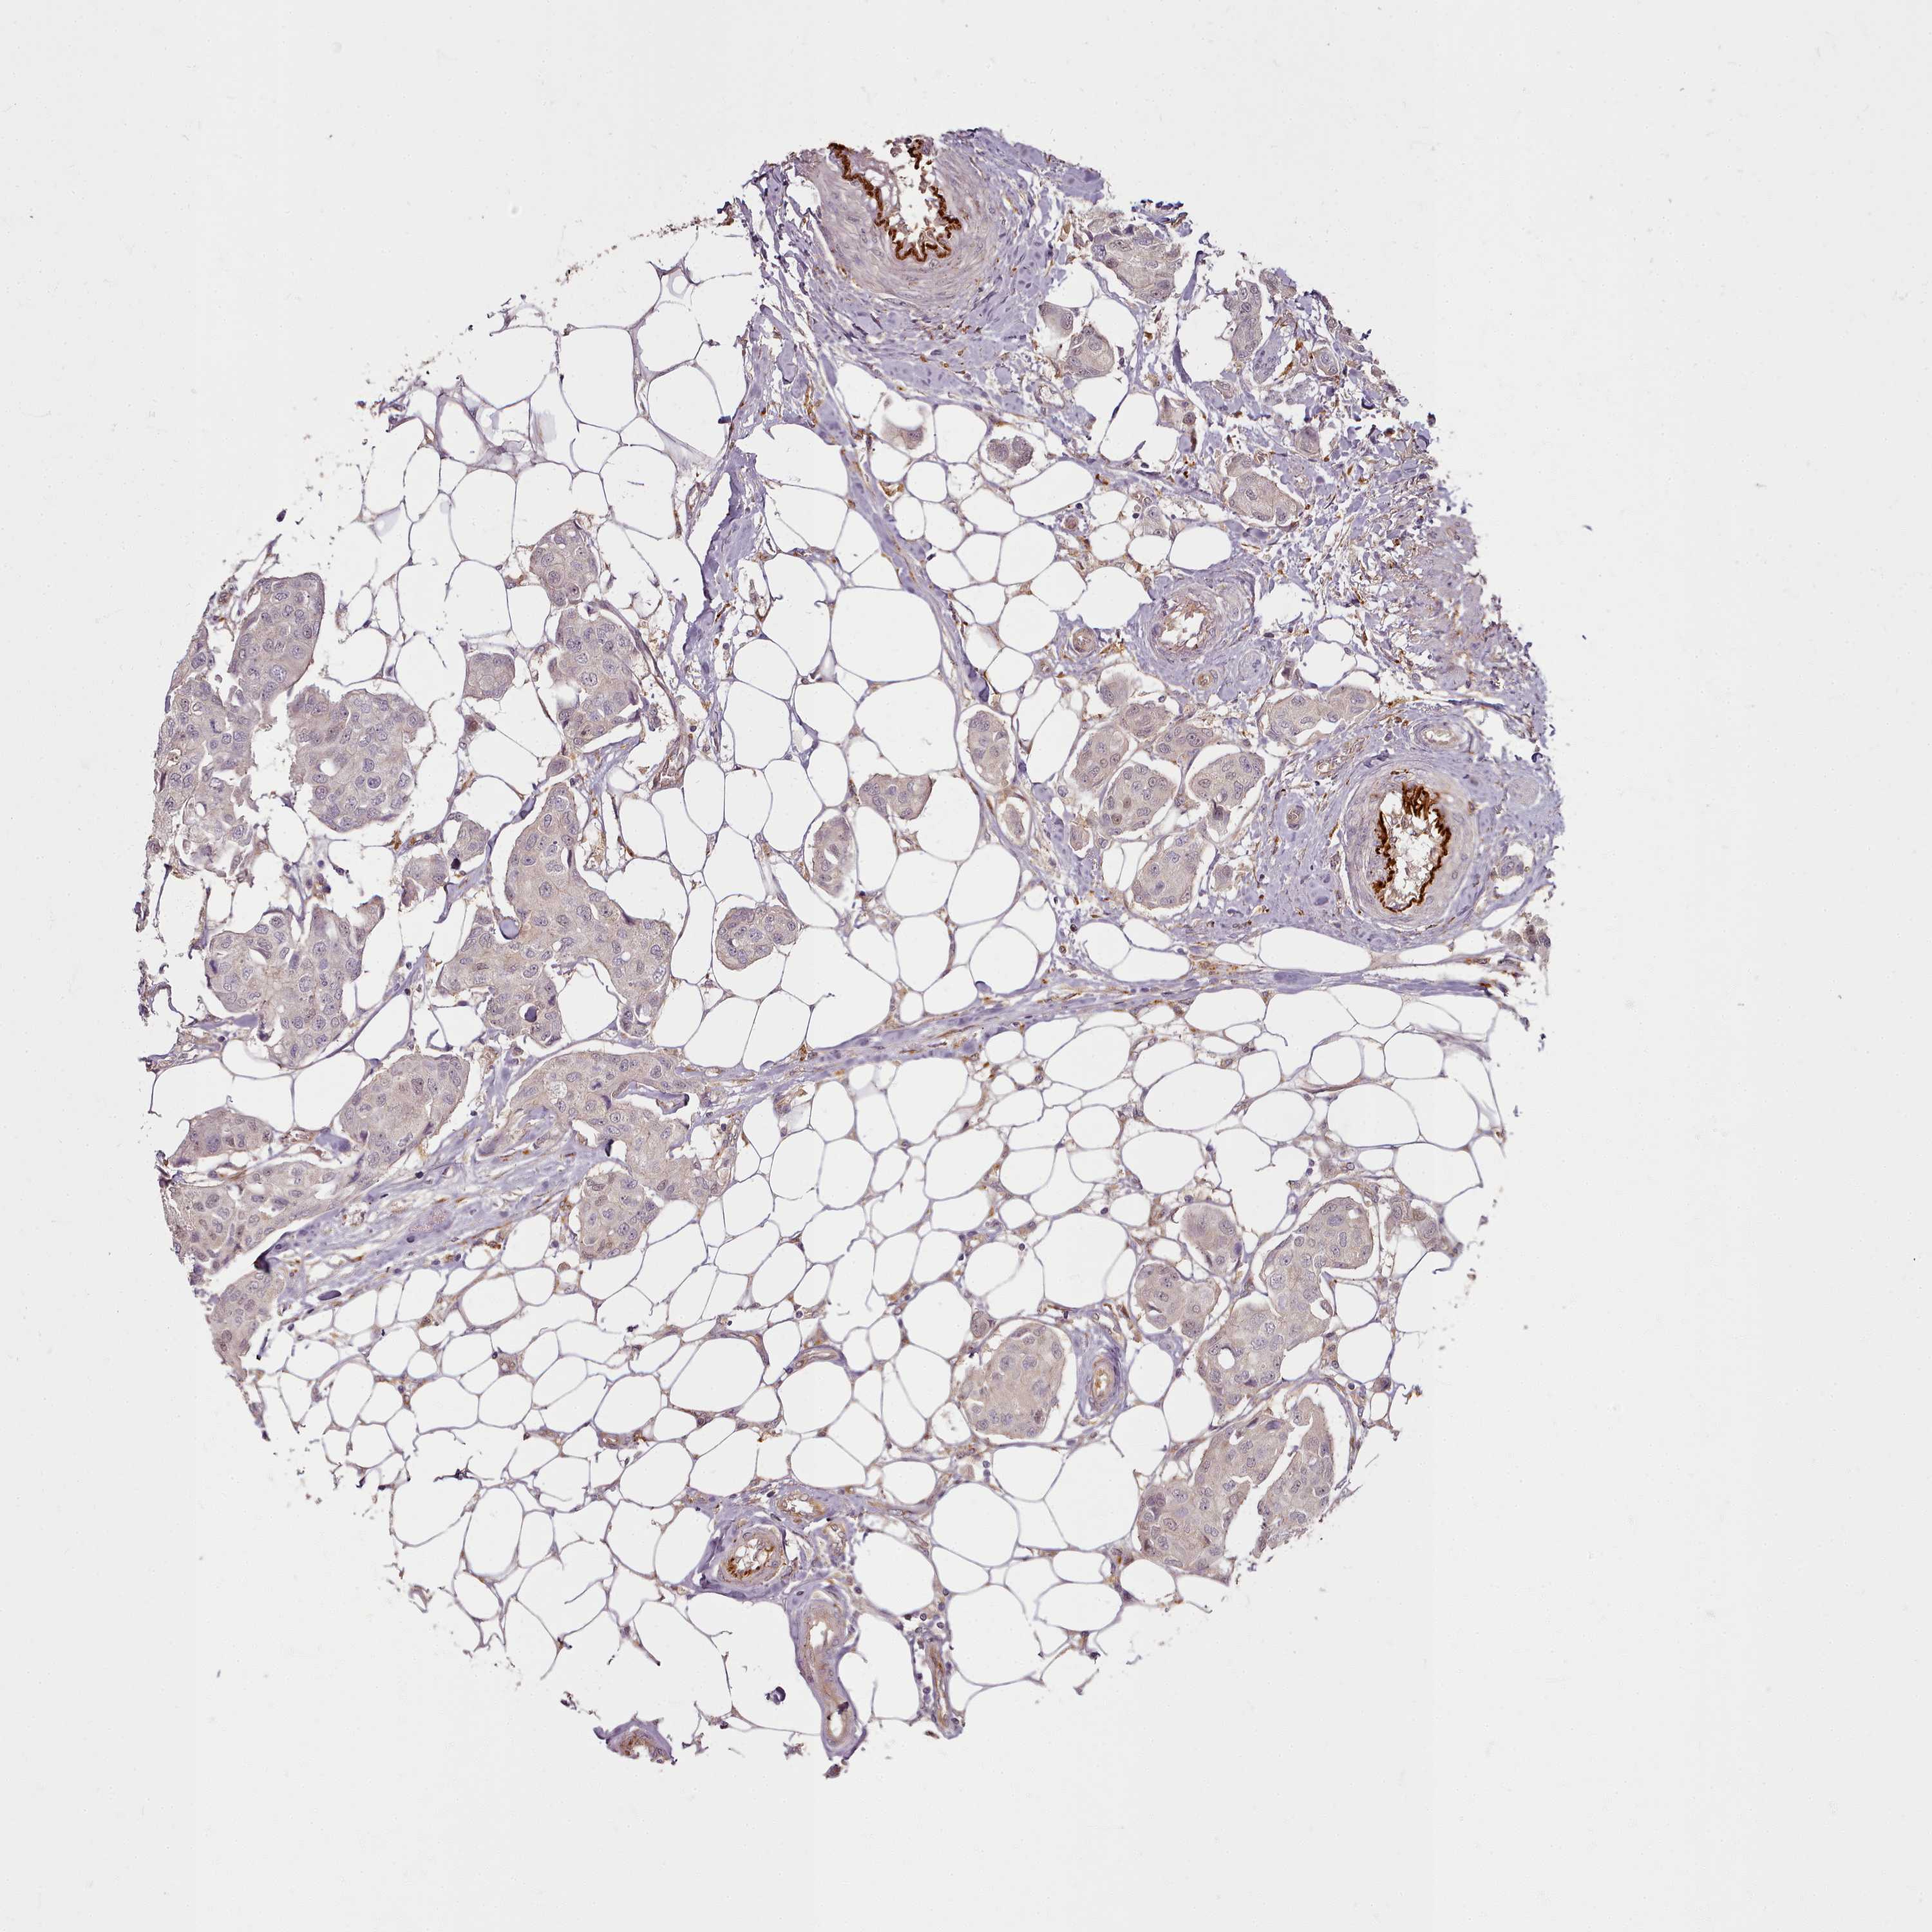

CANCER BREAST CANCER Show tissue menu

Breast cancer

Human cancer